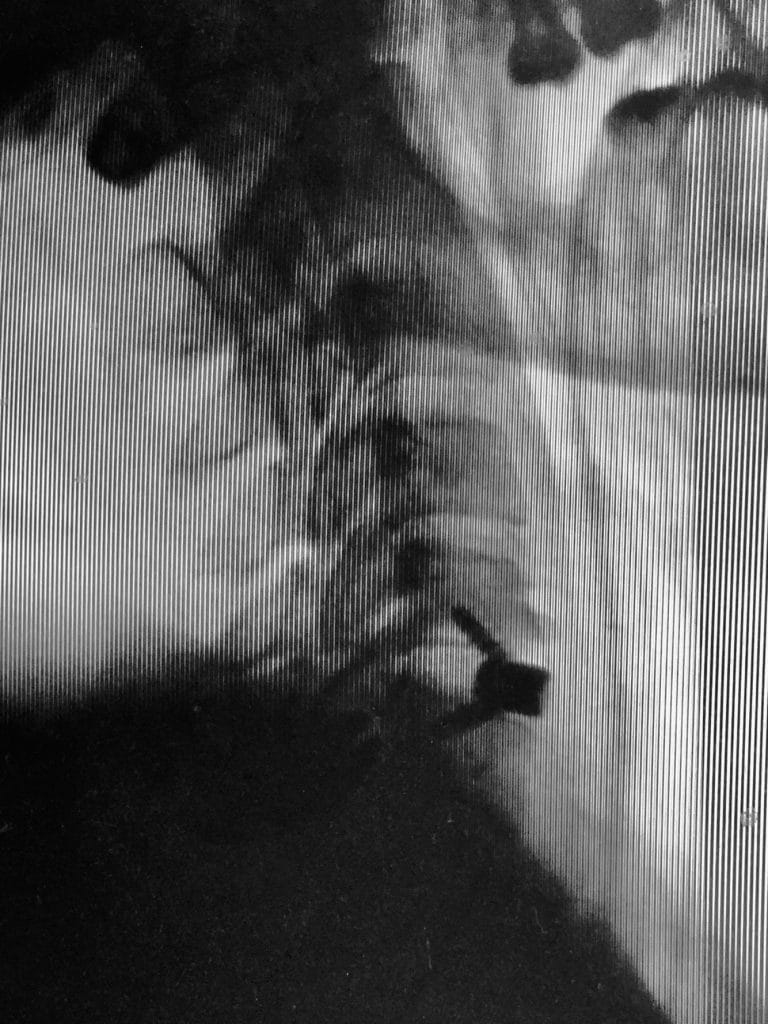

El dispositivo intersomático cervical está indicado para procedimientos de fusión intersomática cervical por vía anterior en pacientes con esqueleto maduro